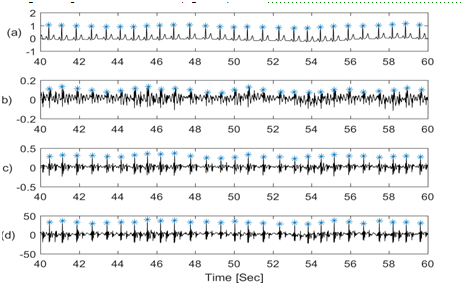

The goal of this study is to detect respiration information from various physiological signals including: chest wall movement, ECG, chest galvanic skin response (GSR) and SCG signals. All respiration signals considered will be compared with simultaneously acquired lung volume changes from direct respiration airflow measurements. This permits the identification of signals that best correlate with the direct respiration measurement. Figure 1 shows the physiological signals of interest plotted over a period of 20 seconds. The signals showed a period of oscillation that is potentially similar to the lung volume signal.

Figure 1 Physiological signals in time domain showing (a) Respiratory airflow, (b) Lung volume, (c) chest wall movement by piezo-electric sensor, (d) ECG, (e) Galvanic skin response, (f) SCG in craniocaudal axis, (g). SCG in lateral axis, (h) SCG in dorsoventral axis. All other signals (c to h) appear to potentially have components at the respiratory frequency, which indicates that respiratory information may be extracted from these signals.